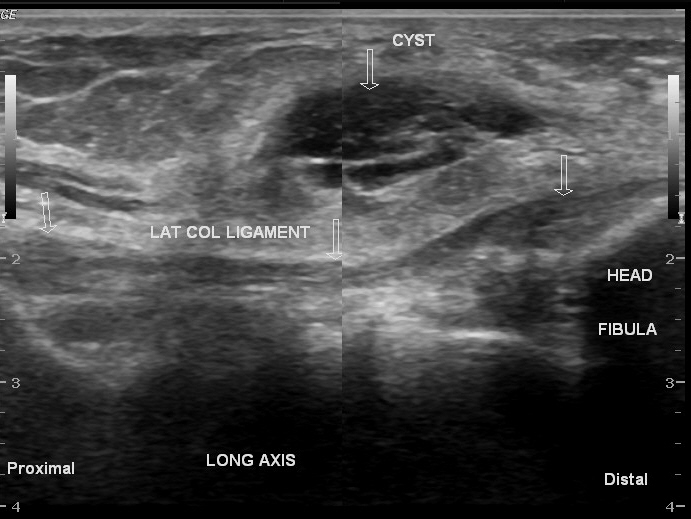

Ecografía (Ultrasonido) — Estudio de primera línea

Rol: Confirmación diagnóstica, guía para aspiración/infiltración, evaluación de relaciones vasculares.

- Hallazgos típicos: Lesión anecoica o hipoecoica, bien definida, con refuerzo acústico posterior. Puede ser multilobulada.

- Contenido: Líquido viscoso (puede aparecer con ecos internos finos).

- Pedículo: A veces se identifica el tracto que comunica con la articulación.

- Doppler: Ausencia de vascularización interna (clave para diferenciar de tumores sólidos).

Ventaja: Dinámico, barato, accesible, sin radiación.